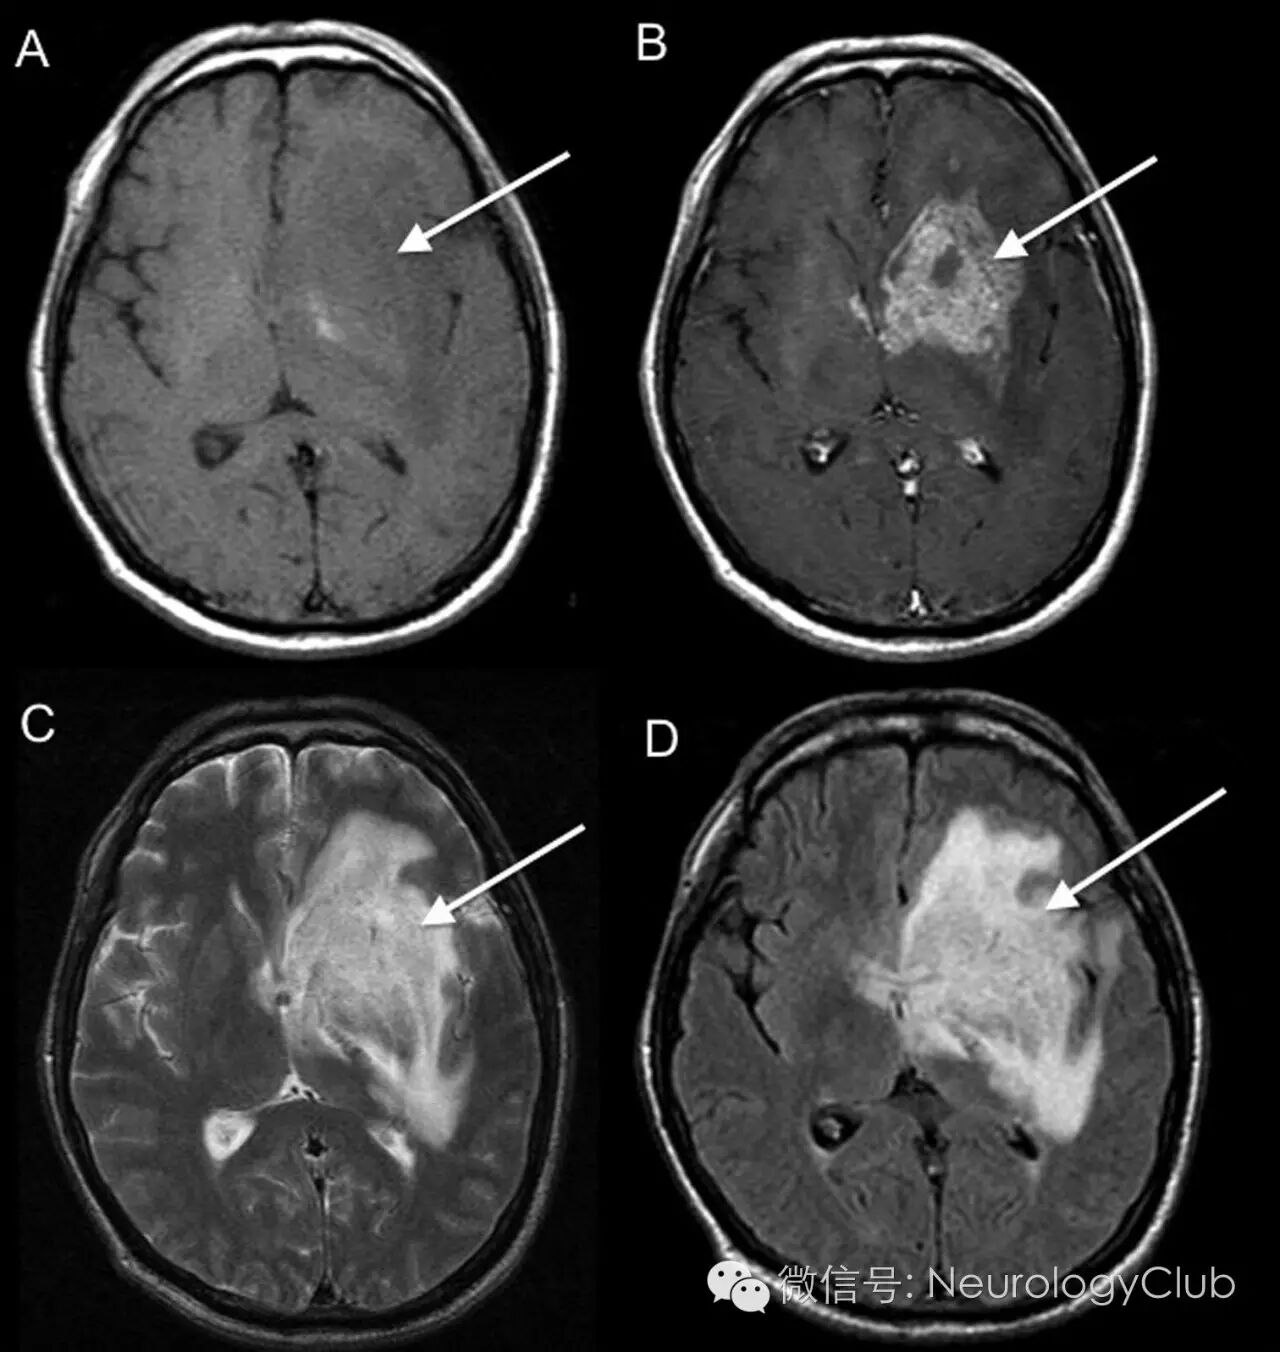

头颅CT提示单发的52×41×38mm不均匀强化肿块,中心位于左侧豆状核,伴周围白质低密度,延伸至左侧额叶、颞叶和顶叶,中线偏移7mm(图1)。初步诊断考虑胶质母细胞瘤。

(图1:增强CT提示单发的52×41×38mm不均匀强化肿块,中心位于左侧豆状核[箭],中线偏移7mm,高度怀疑多形性胶质母细胞瘤